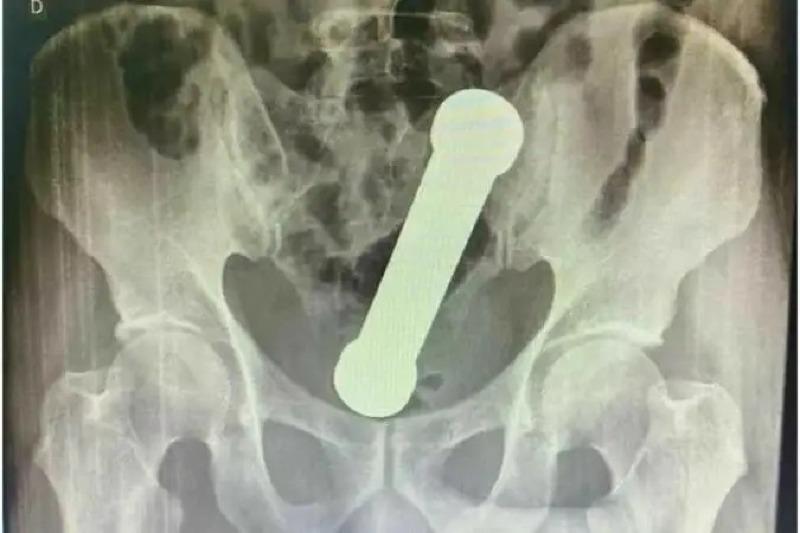

Um paciente, ainda não identificado, fugiu do Hospital Vale do Guaporé, em Pontes e Lacerda (a 444 km de Cuiabá), na tarde deste sábado (21), após passar por uma cirurgia para retirada de um objeto estranho introduzido na região anal.